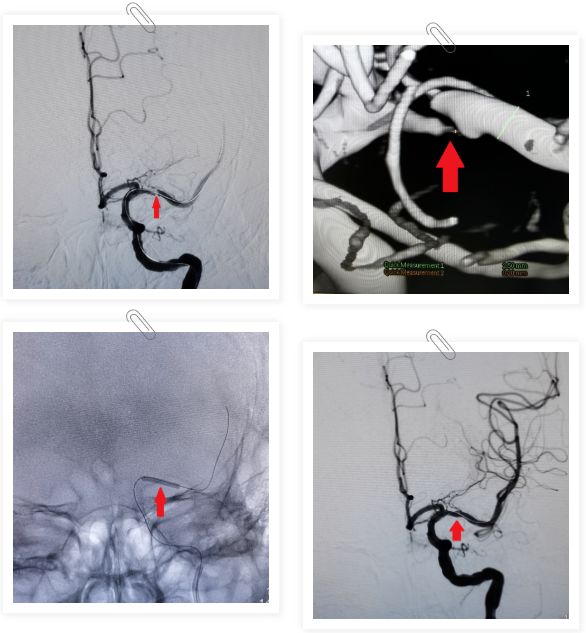

入院后,茂名市人民医院神经内科一区介入手术团队对张先生的病情和身体状况进行了综合评估,经检查,发现张先生左侧大脑中动脉粥样硬化伴极重度狭窄(92%),脑灌注明显不足。据相关研究显示,该疾病在神经血管领域仍然是一种具有挑战性的疾病,无论采用药物治疗、颅内外血管搭桥术或支架植入术,患者术后身体均受到不同程度的损伤。经过充分细致的讨论,团队建议运用颅内药物涂层球囊为张先生进行治疗。据悉,该项技术原理是通过球囊扩张狭窄部位,并通过球囊体上的特殊药物,以达到长期改善颅内供血的治疗效果。相较于传统的支架介入治疗,该技术无需置入金属支架,有望更有效降低手术风险和再狭窄复发率,取得更优预后。

在经过患者和家属充分知情同意后,茂名市人民医院神经内科介入手术团队在8月8日为患者进行了手术。在团队的密切配合下,手术过程顺利,成功修复了狭窄血管,脑灌注也恢复正常。术后,在医护人员的精心护理下,张先生的恢复水平已经达到出院标准,现在已经出院回家休养。在张先生出院后,神经内科一区医护团队将继续密切关注张先生回家后的恢复状况、定期随访,希望能为更多像张先生一样的患者带来康复的福音。